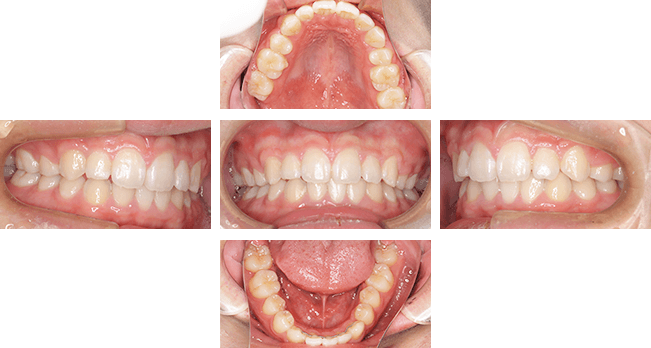

上顎前突case1. 10代女性(治療期間4年11か月)

| 主訴 | 前歯が出ている(審美障害) |

| 診断名 | 上顎前突、過蓋咬合、空隙歯列弓 |

| 初診時年齢 | 9歳5か月 |

| 性別 | 女性 |

| 動的治療期間 | 4年11か月 |

| 主な矯正装置 | 咬合斜面板、アクティブプレート、ヘッドギア、マルチブラケット装置 |

| 抜歯/非抜歯 | 非抜歯 |

| 治療費用(税込) | 検査診断:44,000円 装置料:550,000円 調節料:5,500円×54回 |

| 副作用とリスク | 成長期からの治療(早期治療)になるので、治療期間が長くなります。そのため、患者さんの協力が非常に重要になります。 |

治療後